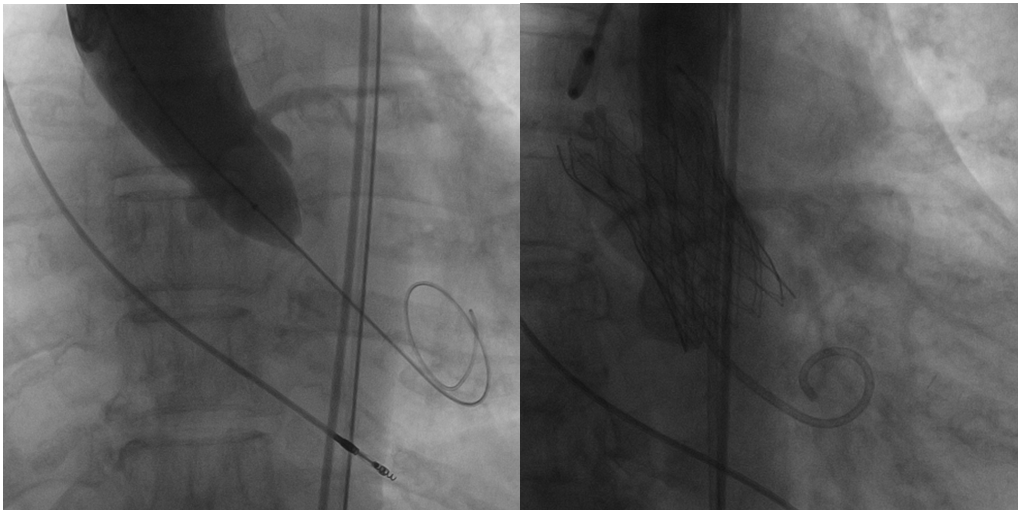

常规消毒铺巾,2%利多卡因局麻,穿刺左锁骨下静脉,置入临时起搏电极至右心室心尖部,连接临时起搏器备用。超声引导下穿刺左股动脉成功后置入7F鞘,送6F猪尾导管至无冠窦底。超声引导下穿刺右股动脉预置2把Proglide缝合器后置入6F鞘,JR造影导管送预塑型加硬导丝至升主动脉,沿加硬导丝送20F大鞘至降主动脉,沿大鞘送6F AL2导管及直头导丝跨主动脉瓣至左室心尖,交换145°猪尾导管送至左室测跨瓣压差为10mmHg,送预塑型加硬导丝至左室心尖部,在加硬导丝支撑下送18mm球囊跨主动脉瓣,临时起搏180次/分、扩张球囊、造影、撤球囊、停起搏,在加硬导丝支撑下送佩嘉23mm自膨瓣跨主动脉瓣,临时起搏180次/分、精确定位后释放瓣膜至极限位、停起搏,造影及经胸超声评估跨膜压差10mmHg、无返流、无明显瓣周漏及心包积液、冠脉未受影响,遂完全释放瓣膜(图6)。经胸超声评估瓣膜位置良好,窦性心律,63次/分,遂撤出瓣膜输送系统。撤出20F大鞘、右侧股动脉入路使用预置Proglide缝合器处理后,对侧翻山造影未见右股动脉出血,无血肿、右足背动脉搏动好。用Angioseal血管闭合器处理左侧股动脉穿刺处,穿刺处无出血及血肿、左足背动脉搏动好。双侧股动脉加压包扎。术中给肝素5000单位。保留临时起搏电极,安返病房。术后24小时下床活动、48小时后拔除临时起搏电极、3天后康复出院。

(图6 18mm球囊预扩、佩嘉23mm自膨瓣完全释放)